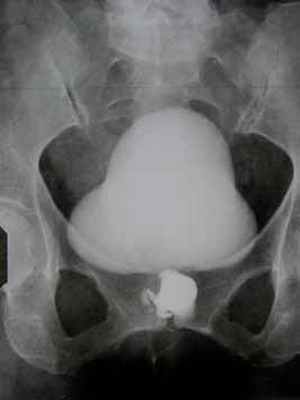

На экскреторной урограмме - анатомо-функциональных изменений со стороны почек, мочеточников и мочевого пузыря не выявлено. Выполнена восходящая уретроцистография, при которой визуализируется дивертикул уретры неправильной округлой формы диаметром до 4,5-5,0 см, дефектов контрастирования в проекции этого образования не обнаружено (рисунок 2).

![]() |

| Рисунок 2. Восходящая уретроцистография, при которой визализируется дивертикул уретры |

| Рисунок 3. Контрастирование дивертикула после микции |

После мочеиспускания определяется скопление контрастного вещества в дивертикуле уретры (рисунок 3).